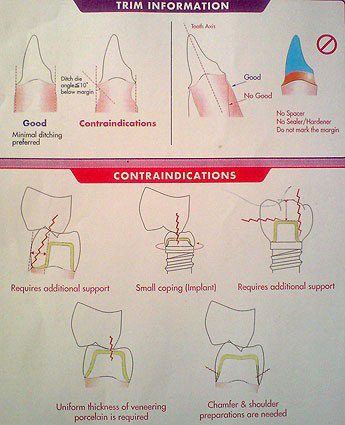

میزان تراش